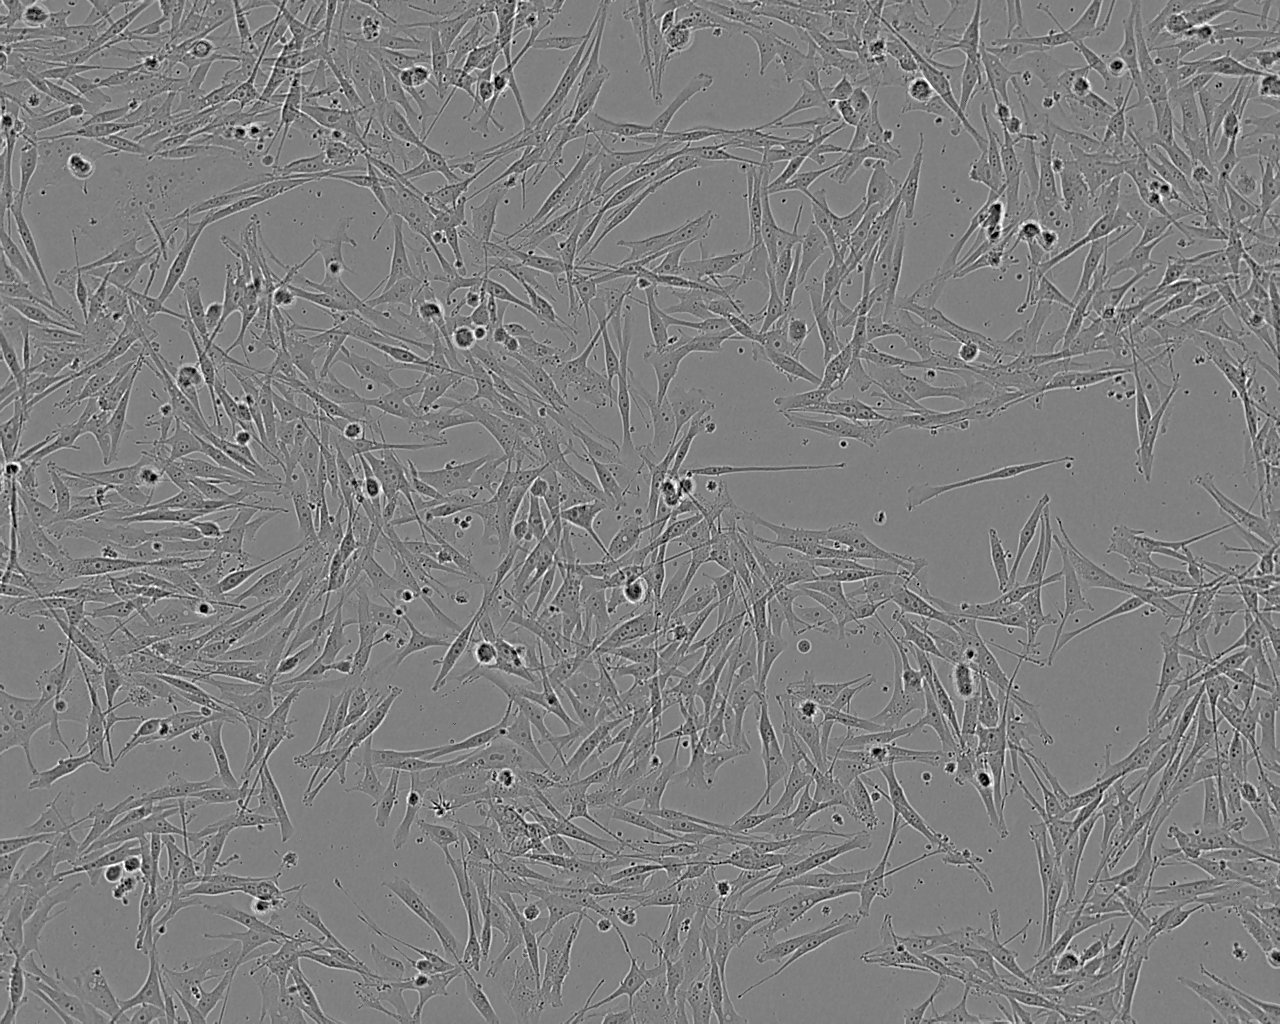

Established from a vaginal malignant melanoma of a 65 year-old female with blood type B. Cells produce melanin and can support the replication of influenza C virus.

Split sub-confluent cultures (70-80%) 1:3 to 1:6 i.e. seeding at 2-4x10,000 cells/cm² using 0.05% trypsin or trypsin/EDTA; 5% CO₂; 37°C.

Ham's F10 or RPMI 1640 + 2mM Glutamine + 10-20% Foetal Bovine Serum (FBS).